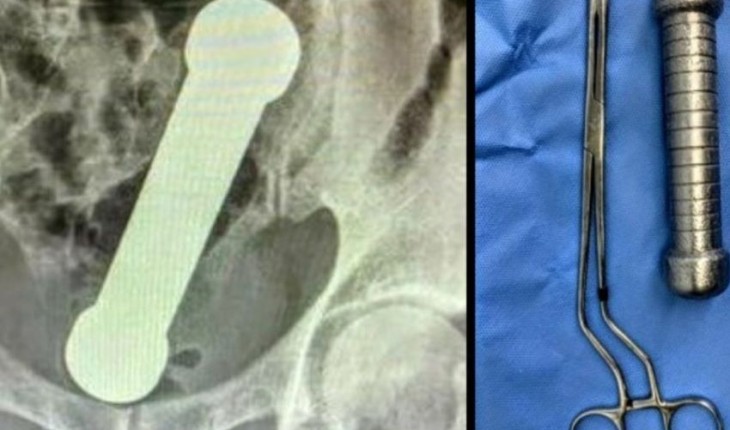

Caso ocorreu na cidade de Goiânia e vítima foi socorrida estando consciente.